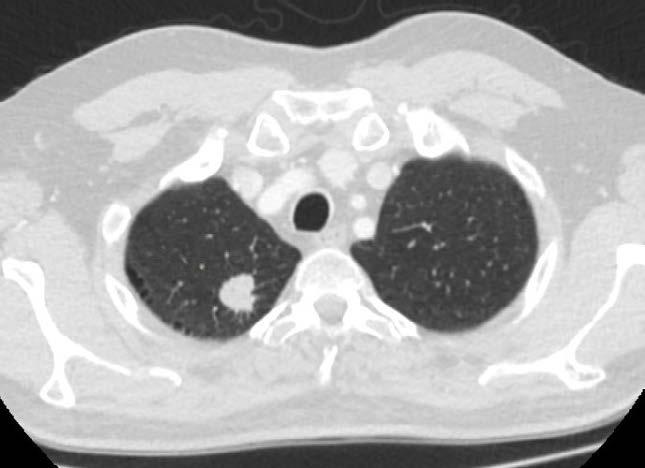

Mynd 6-1 Lítið lungnakrabbamein í hægra lunga (ör) sem fannst við skimun með tölvusneiðmyndum.

Með tilkomu tölvusneiðmyndatækni (TS) varð unnt að finna mun smærri hnúta í lungum en áður var mögulegt með hefðbundnum röntgenmyndum (mynd 6-1). Á síðustu áratugum hefur verið efnt til stórra framvirkra samstarfsverkefna, bæði í Bandaríkjunum og Evrópu. Fyrstu rannsóknir á skimun með TS voru gerðar í Japan og fyrsta alþjóðlega rannsóknin benti til þess að unnt væri að finna um